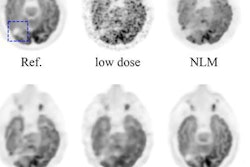

Meanwhile, artificial intelligence is finding use in the realms of both molecular imaging and nuclear medicine. Researchers from Stanford University have trained a deep-learning algorithm to process PET image data acquired with ultralow doses of radiopharmaceuticals, so scans can be performed at only 1% of current dose levels.